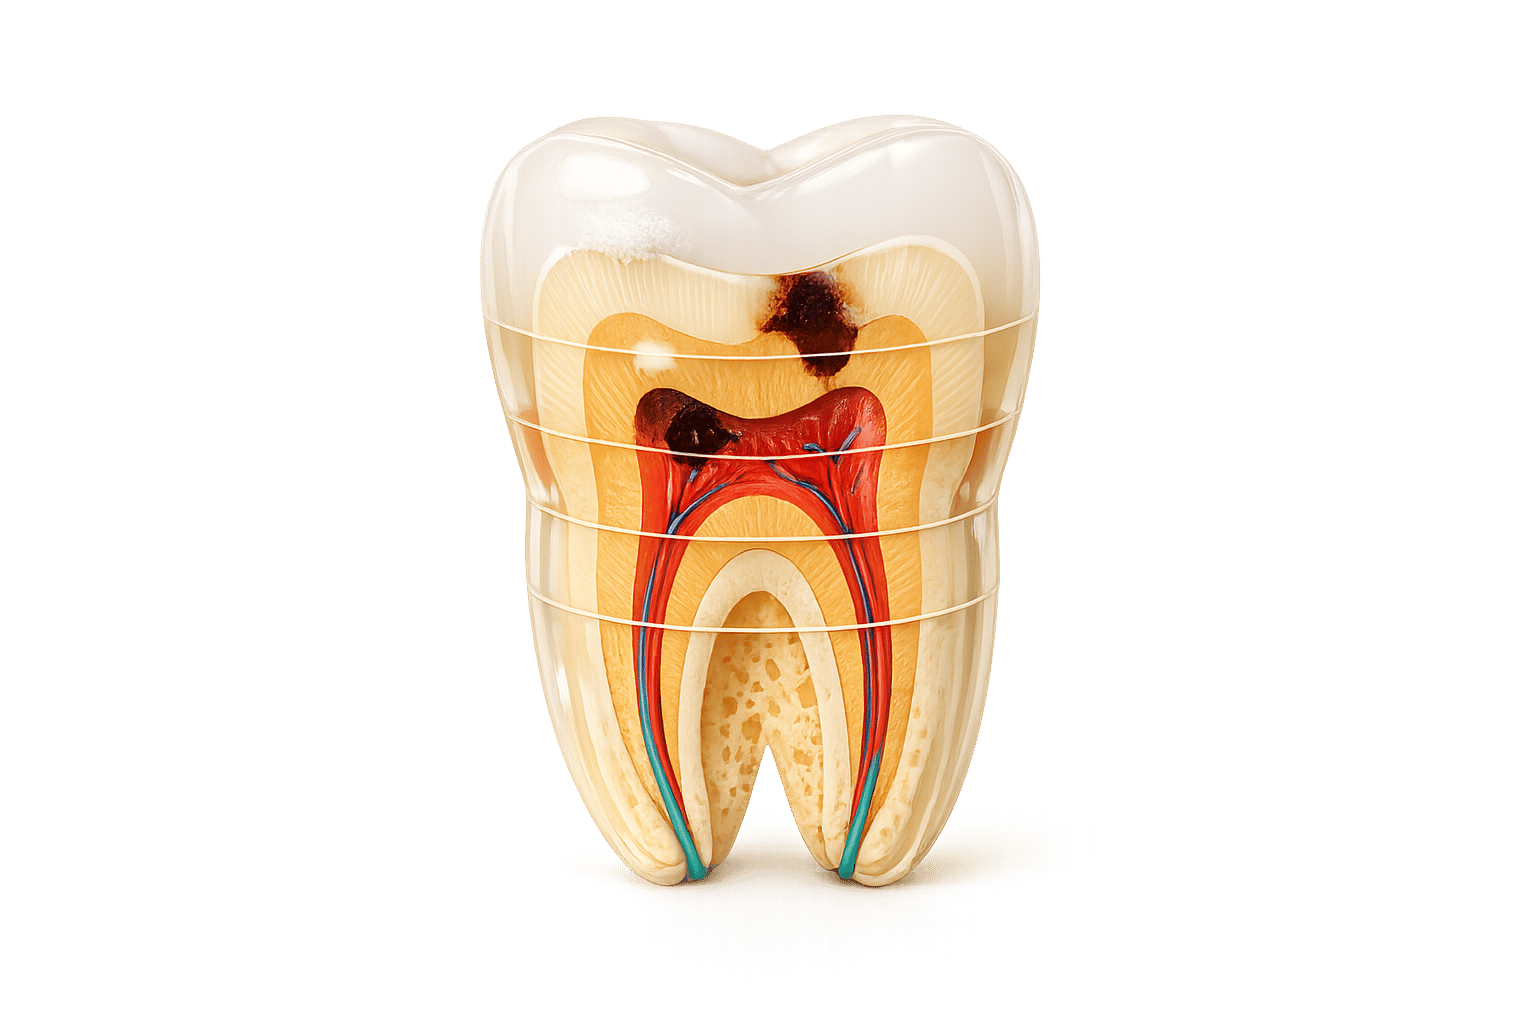

6. So lässt sich Karies vorbeugen

Die Kosten und Unannehmlichkeiten von Kariesbehandlungen lassen sich durch präventive Zahnpflege vermeiden – ein entscheidender Schritt für Ihre Zahngesundheit.

Bakterien im Zahnbelag verwandeln Zucker und Kohlenhydrate in Säuren, die den Zahnschmelz angreifen. Daher ist es wichtig, den Konsum von zuckerhaltigen Lebensmitteln und Getränken wie Süßigkeiten, Softdrinks, Fruchtsäften und Ketchup zu reduzieren.